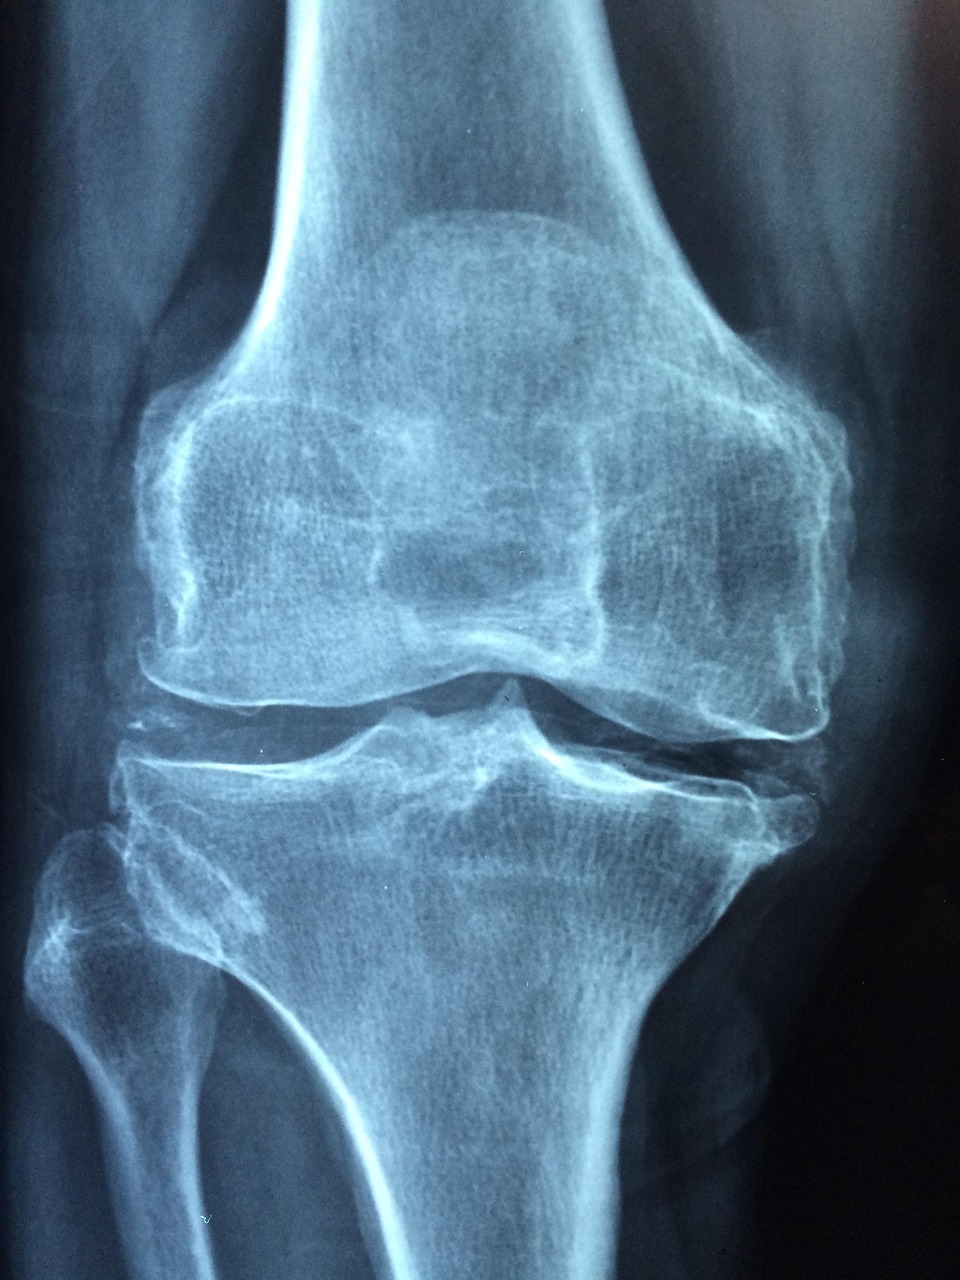

무릎 관절 엑스레이 사진

40대가 되면 가장 먼저 느끼는 신체 변화 중 하나가 관절에서 오는 불편함입니다. 무릎을 구부리거나 계단을 오를 때 통증이 생기거나, 아침에 일어났을 때 관절이 뻣뻣한 느낌을 받을 수 있습니다. 이러한 증상은 단순한 노화 현상이 아니라, 연골의 마모와 윤활액 감소로 인해 관절의 마찰이 증가했기 때문입니다. 특히 무릎, 손목, 어깨, 고관절 등 자주 사용하는 부위에서 이러한 변화가 두드러지게 나타납니다. 중년 이후 체중이 증가하면 하중을 받는 관절에 더 많은 부담이 가해져 증상이 악화될 수 있습니다. 이 시기에는 관절염(퇴행성 관절염, 류마티스 관절염 등) 발생 위험이 높아지므로 정기적인 건강 검진이 중요하며, 초기 증상이 보일 때 즉시 대응하는 것이 필요합니다. 또한 관절 내 연골은 한 번 닳으면 재생되지 않기 때문에 사전 예방과 일상 속 관리가 필수적입니다. 관절의 통증이나 불편함을 단순한 ‘노화’로만 생각하지 말고, 생활 습관을 개선하는 적극적인 자세가 필요합니다.